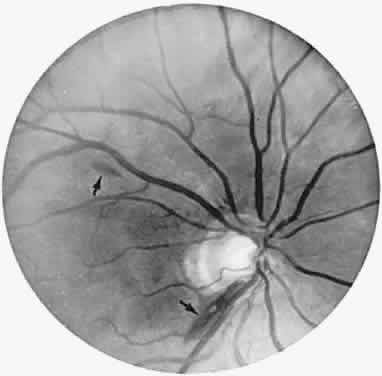

With acute infarction, the retina becomes opaque and takes on a creamy or gray appearance. Atheromatous material in the form of “bright plaques” of cholesterol or other microemboli may be seen, especially lodged at arterial bifurcations (Fig. 5). Segmental arteriolar mural opacification (see Fig. 5D) may follow retinal microembolization by weeks to months, and such sheathing may be as useful as the recognition of the cholesterol embolus itself.43 ERG may show diminished B-wave amplitude, a finding indicating inner retinal ischemia. Weeks following retinal infarction, the optic disc becomes pale, and the arterial tree becomes narrowed in the sector corresponding to the arterial occlusion.

Fig. 5. Retinal microembolic phenomena. A. Bright cholesterol plaque (arrow) impacted at an arterial bifurcation. Thin crystal does not obstruct flow. B. Cholesterol crystals in disc vessels (arrows). Often, the plaque appears larger than the vessel diameter. C. Infarcted opaque retina. The artery contains emboli (? fibrin platelets) that have obstructed flow. D. Reactive opacification of the arterial wall. Fluorescein angiography demonstrated flow through this formerly occluded vessel.